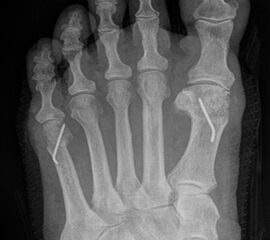

Abb. 7 a, b: Typ II Deformität mit prä- (a) und postoperativem Röntgenbild (b) mit K-Draht Osteosynthese und gleichzeitiger Hallux valgus Korrektur.

Abb. 8 a, b, c: Typ III Deformität mit prä- (a) und postoperativem Röntgenbild (b, c) mit Schrauben-Osteosynthese.

Abb. 9 a, b: Typ III Deformität mit prä- (a) und postoperativem Röntgenbild (b).